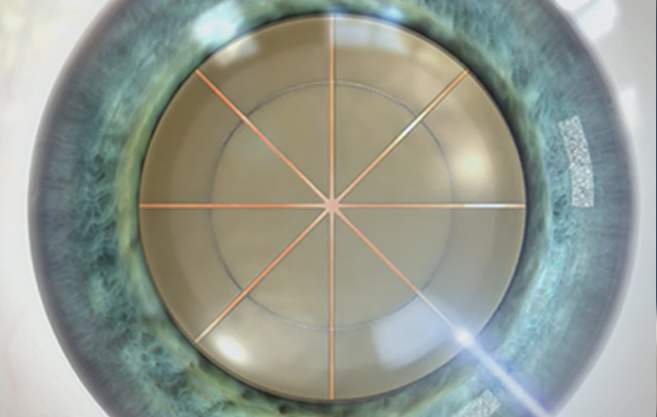

수정체 전낭 절개시 완벽한 원이

완벽한 시력 결과를 낳습니다.

올레이저 노안백내장

정확하고 매끄러운

레이저 절개

vs

수정체 파쇄